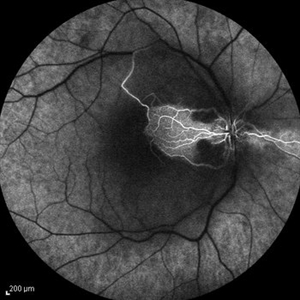

Behcet's Disease Behcet's DiseaseMar 13 2013 by Hamid Ahmadieh, MD Early phase FA of the right eye of a 23-year-old man with retinal vasculitis and branch retinal vein occlusion (BRVO) due to Behcet's disease . Photographer: Solmaz Shahmohammad, Negah Eye Center, Tehran Imaging device: Heidelberg Spectralis Condition/keywords: branch retinal vein occlusion (BRVO), retinal vasculitis